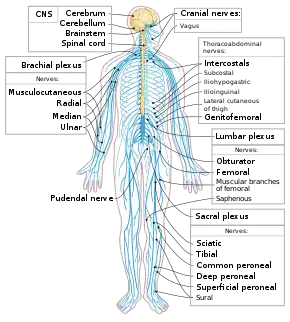

Nervous system

Nervous system The posterior divisions of the sacral nerves.